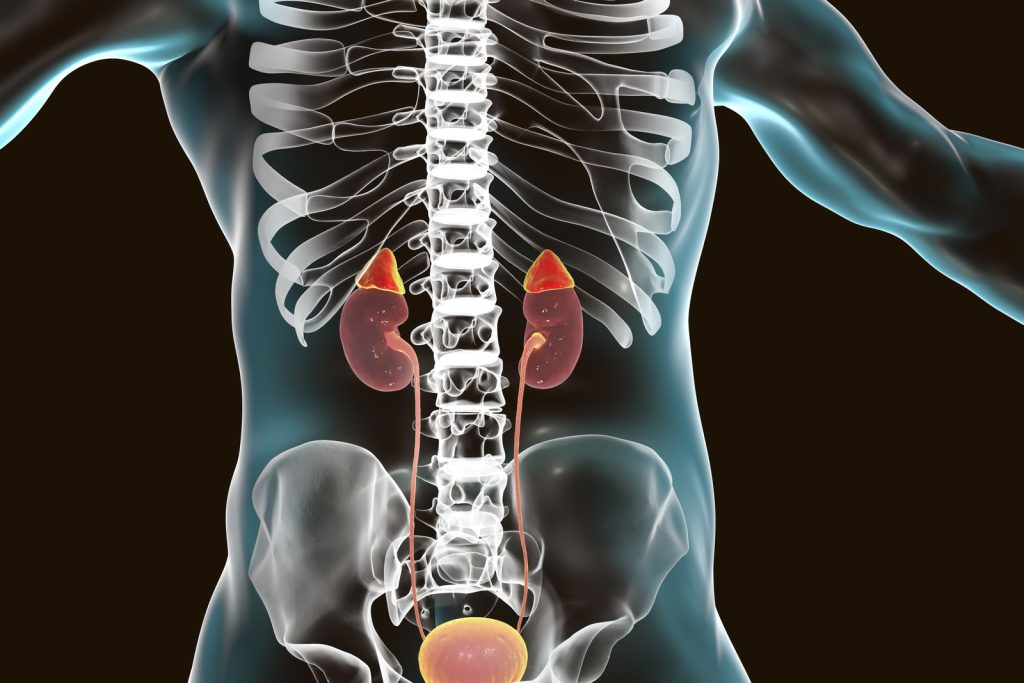

Adrenal tumor

Adrenal insufficiency

Adrenal disorders